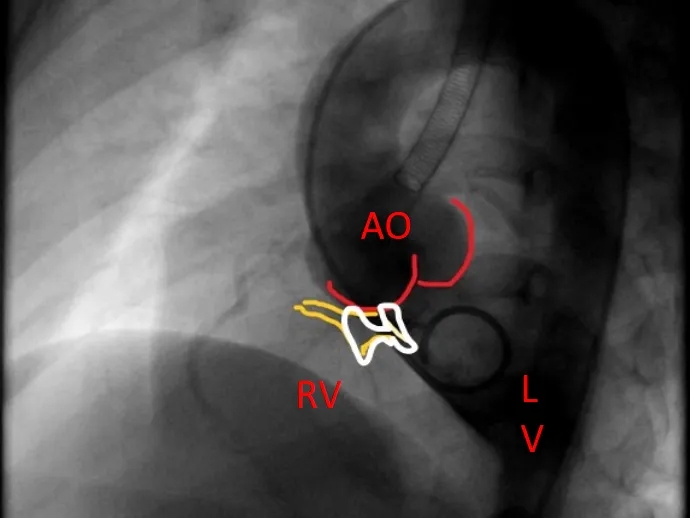

封堵器锁定后呈“蝴蝶状”明显盘状形态,室水平分流完全消失,主动脉瓣反流消失。

牵拉试验,封堵器稳定无移位,释放封堵器后超声下确认无残余分流,无主动脉瓣反流,三尖瓣反流同术前无增加。

大动脉短轴切面,封堵器释放后双盘紧贴间隔,呈现完美“工字形蝴蝶形”,顺应VSD形态及瓣膜形态。

MemoSorb全降解VSD封堵器展现了极佳的顺应性,在通过长隧道、小出口的VSD后,能顺利从“长哑铃”形态展开并固定为贴壁良好的“蝴蝶”形态。术后即刻超声评估显示,伞盘封堵完全,对相邻瓣膜无任何影响,主动脉瓣及三尖瓣均未出现反流。